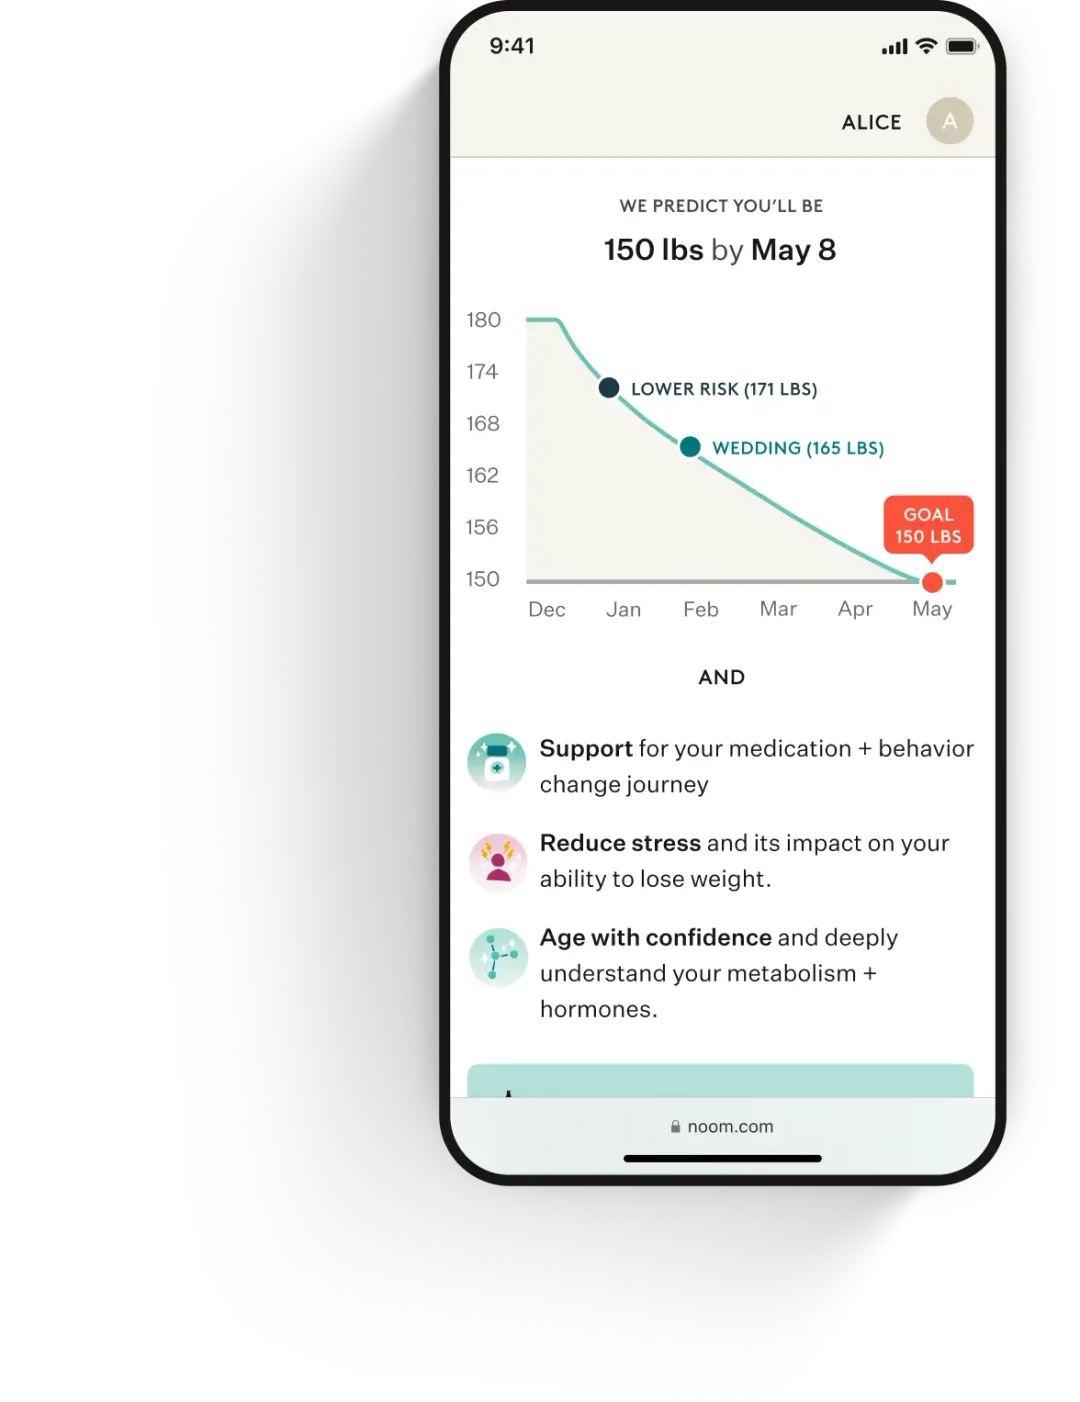

If prescribed, you’ll get a custom plan designed for your goals and biology.

Ongoing care and medication

Stay on track with unlimited access to your clinician and medication refills, where clinically appropriate.